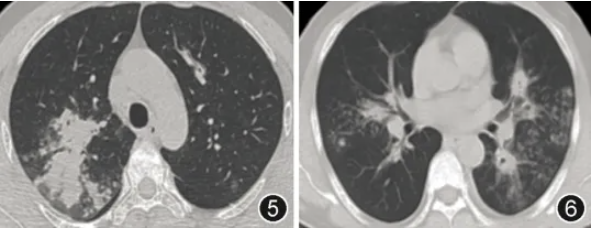

患者男,46岁,主因“咳嗽、咳痰伴发热27 d”于2025年1月27日入院。患者27 d前无明显诱因出现咳嗽、咳少量白黏痰伴发热,体温最高38.6 ℃。当地医院查血甲流IgM(+),胸部CT示双肺斑片影(图1,2),给予口服奥司他韦抗甲流、头孢菌素联合左氧氟沙星抗细菌治疗10 d后,复查胸部CT示双肺多发实变影伴空洞形成(图3,4),经验性加用伏立康唑抗真菌治疗1周后复查胸部CT示病变仍进展(图5,6)。既往史:2型糖尿病8年,口服二甲双胍、阿卡波糖、皮下注射甘精胰岛素治疗,未规律监测血糖;高血压1年,血压最高达170/100 mmHg(1 mmHg=0.133 kPa),未治疗及监测血压。无烟酒嗜好,否认过敏史,家族史无特殊。

图5,6 2025年1月27日(经验性伏立康唑治疗7 d后)胸部CT示双肺多发实变伴空洞影较前进展